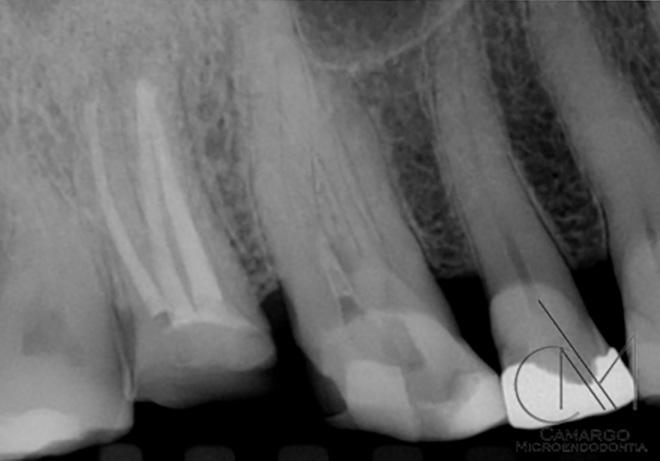

con profundidades de sondaje de 15 mm localizadas y movilidad de clase III. La tomografía computarizada de haz cónico (CBCT) y la radiografía periapical mostra ban pérdida de las paredes vestibular y palatina. No obstante, los dos dientes te nían un buen aporte sanguíneo, como se constató en la prueba de vitalidad pulpar. La paciente quería una segunda opinión y fue derivada a nuestra consulta.

| A Antes del tratamiento ortodóncico. | B CBCT periapical antes del tratamiento periodontal. | C Dientes (13 y 23) ferulizados. | D Bolsa intraósea de 7 mm después de abrir el colgajo. | E Geistlich Bio-Oss® Collagen rellenando el defecto. | F Membrana L-PRF™ bioactiva cubriendo el injerto óseo. |

Fotografías: Scott Froum Fotografías: Scott Froum FIG. 1: Un caso de tratamiento regenerativo de dientes insalvables.